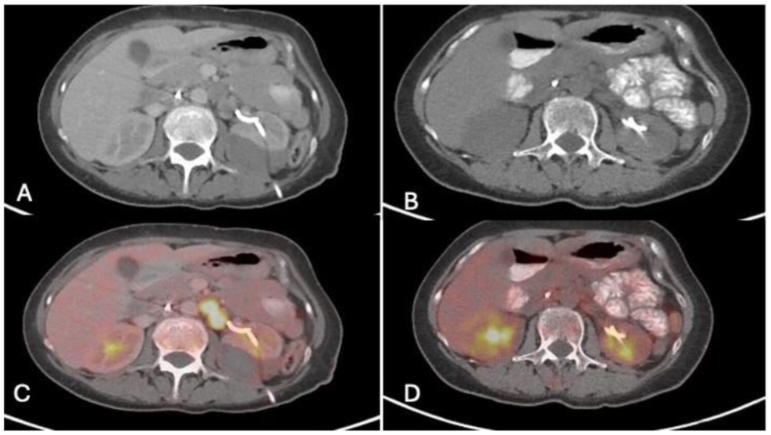

图1. 治疗前后患者的 PET 扫描图像。(a)和(c)显示 2023 年 10 月治疗开始前的盆腔横切片。可见肿大的高代谢后腹膜后淋巴结。(b)和(d)为 2024 年 1 月的影像,显示治疗后后腹膜淋巴结的体积和 FDG 亲近性有所下降。